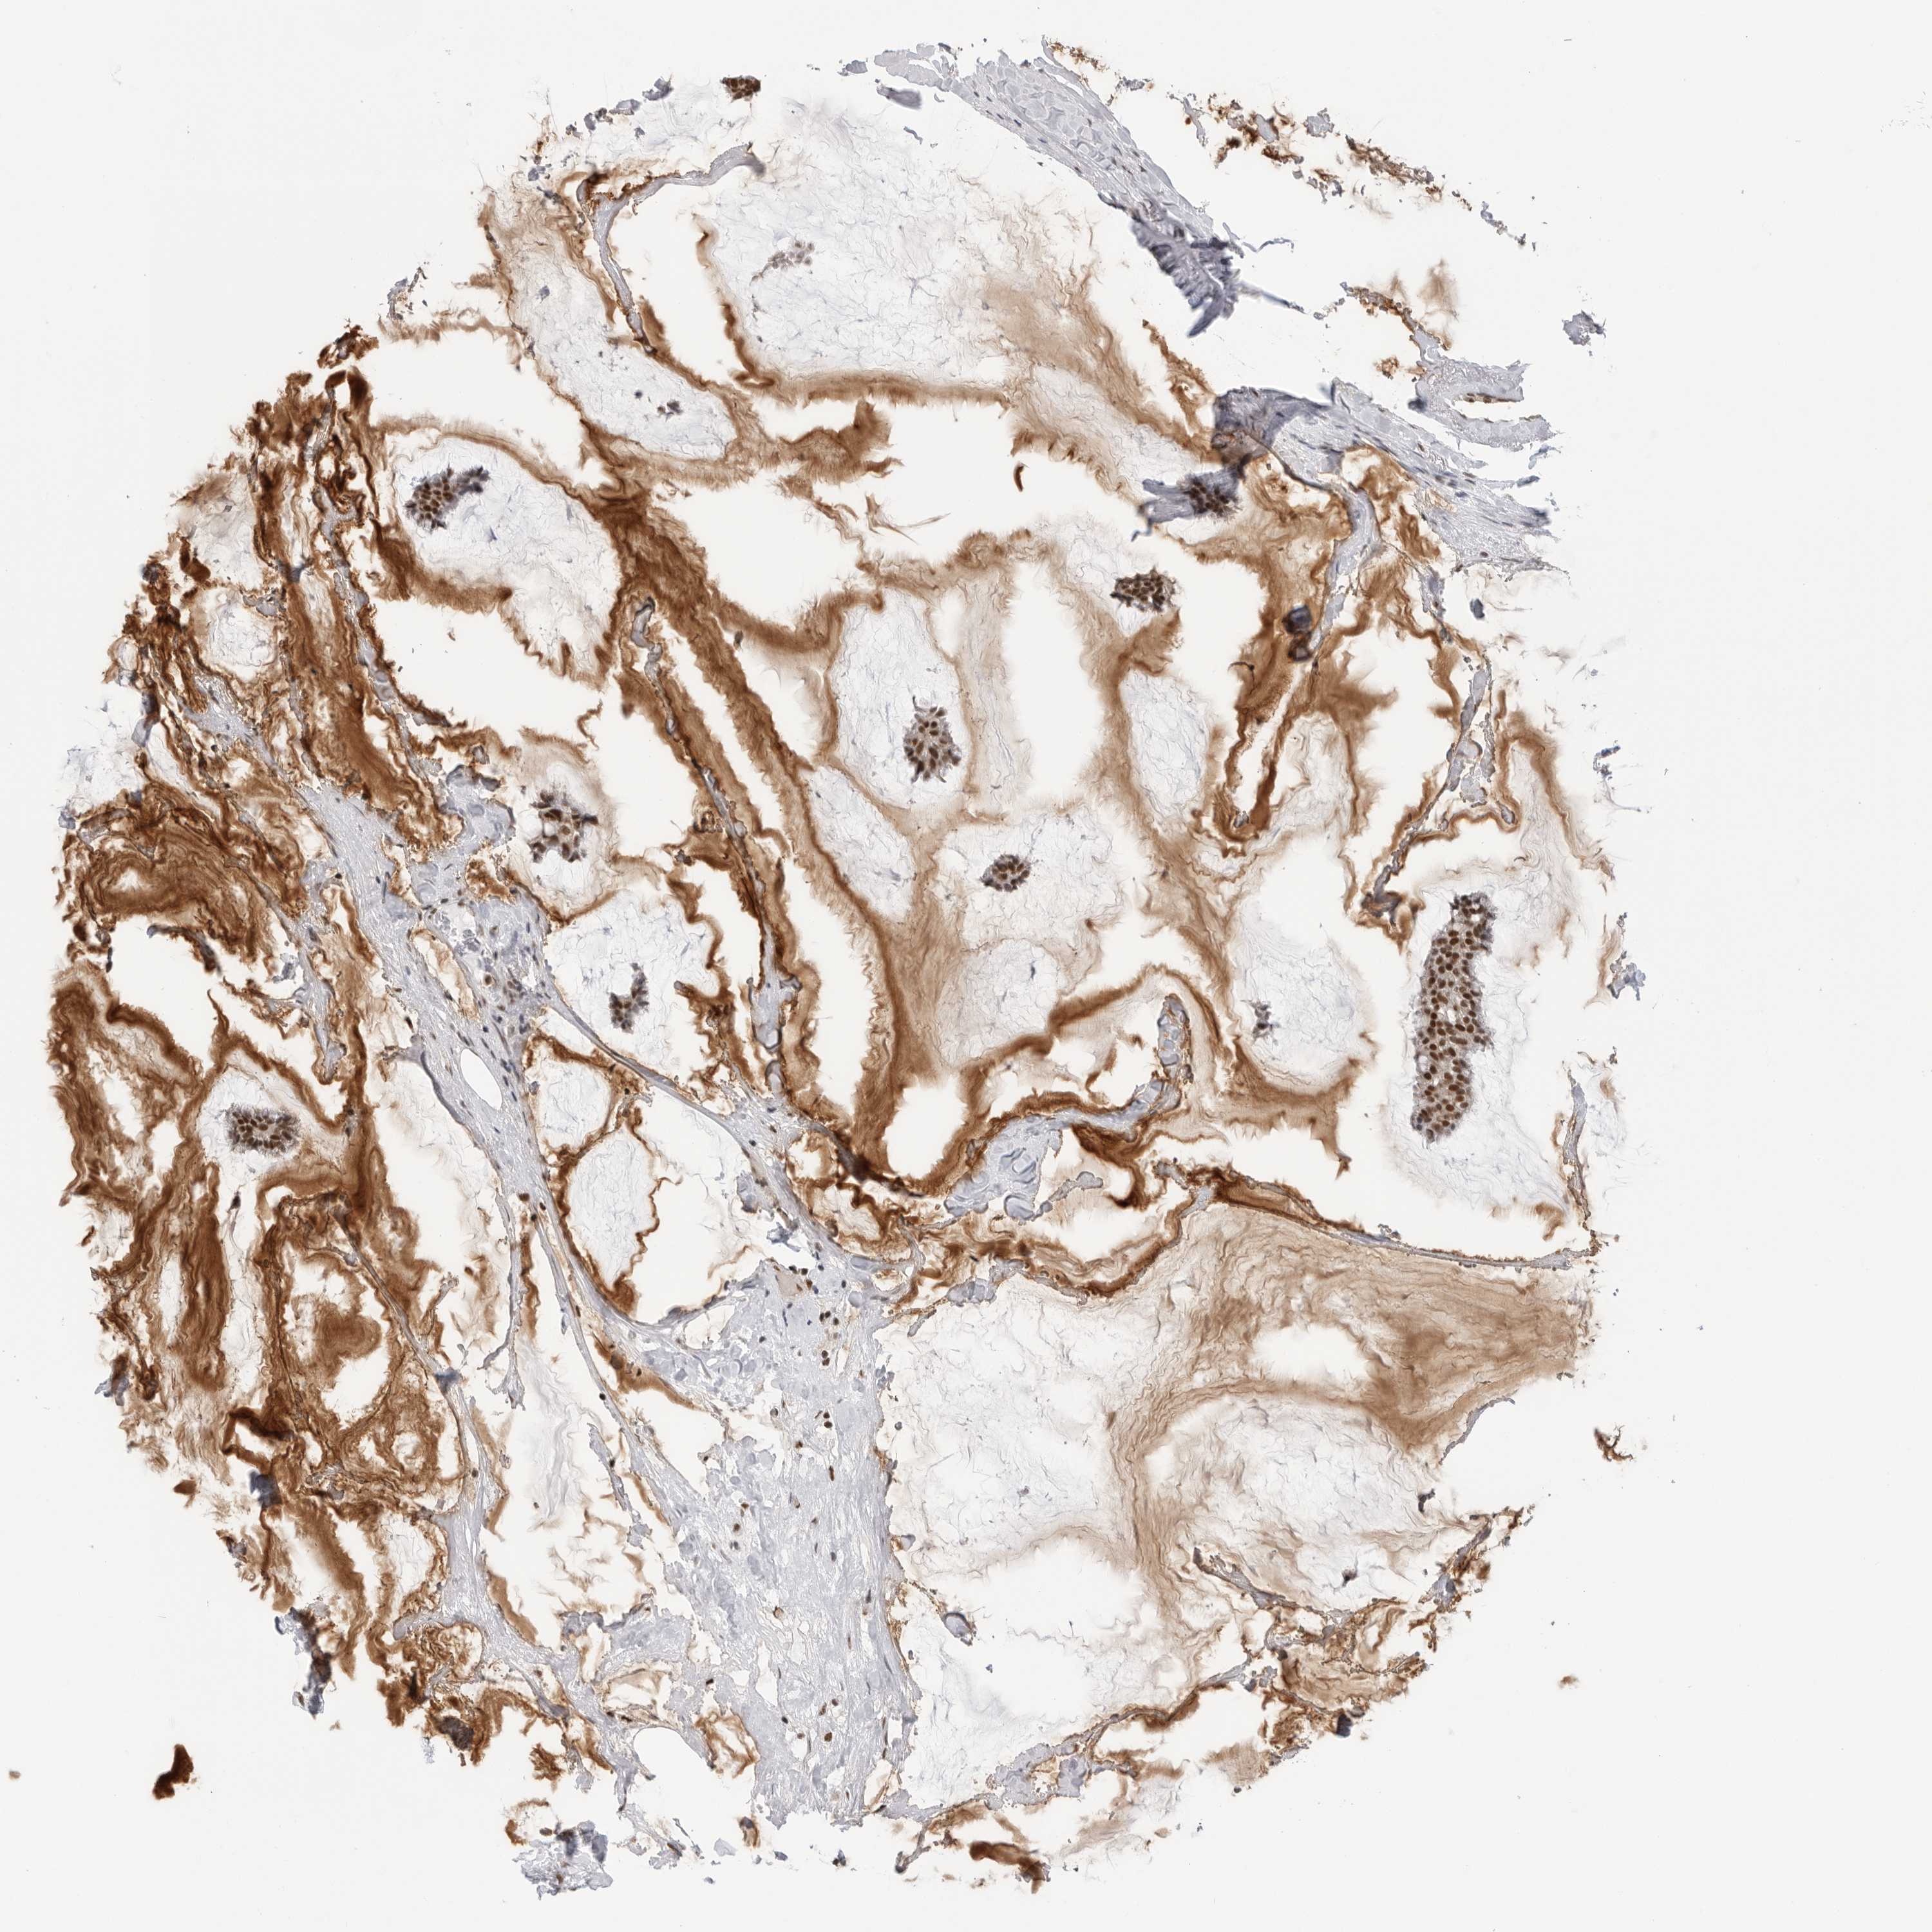

BRCA TCGA BRCA VALIDATION PROTEIN EXPRESSION